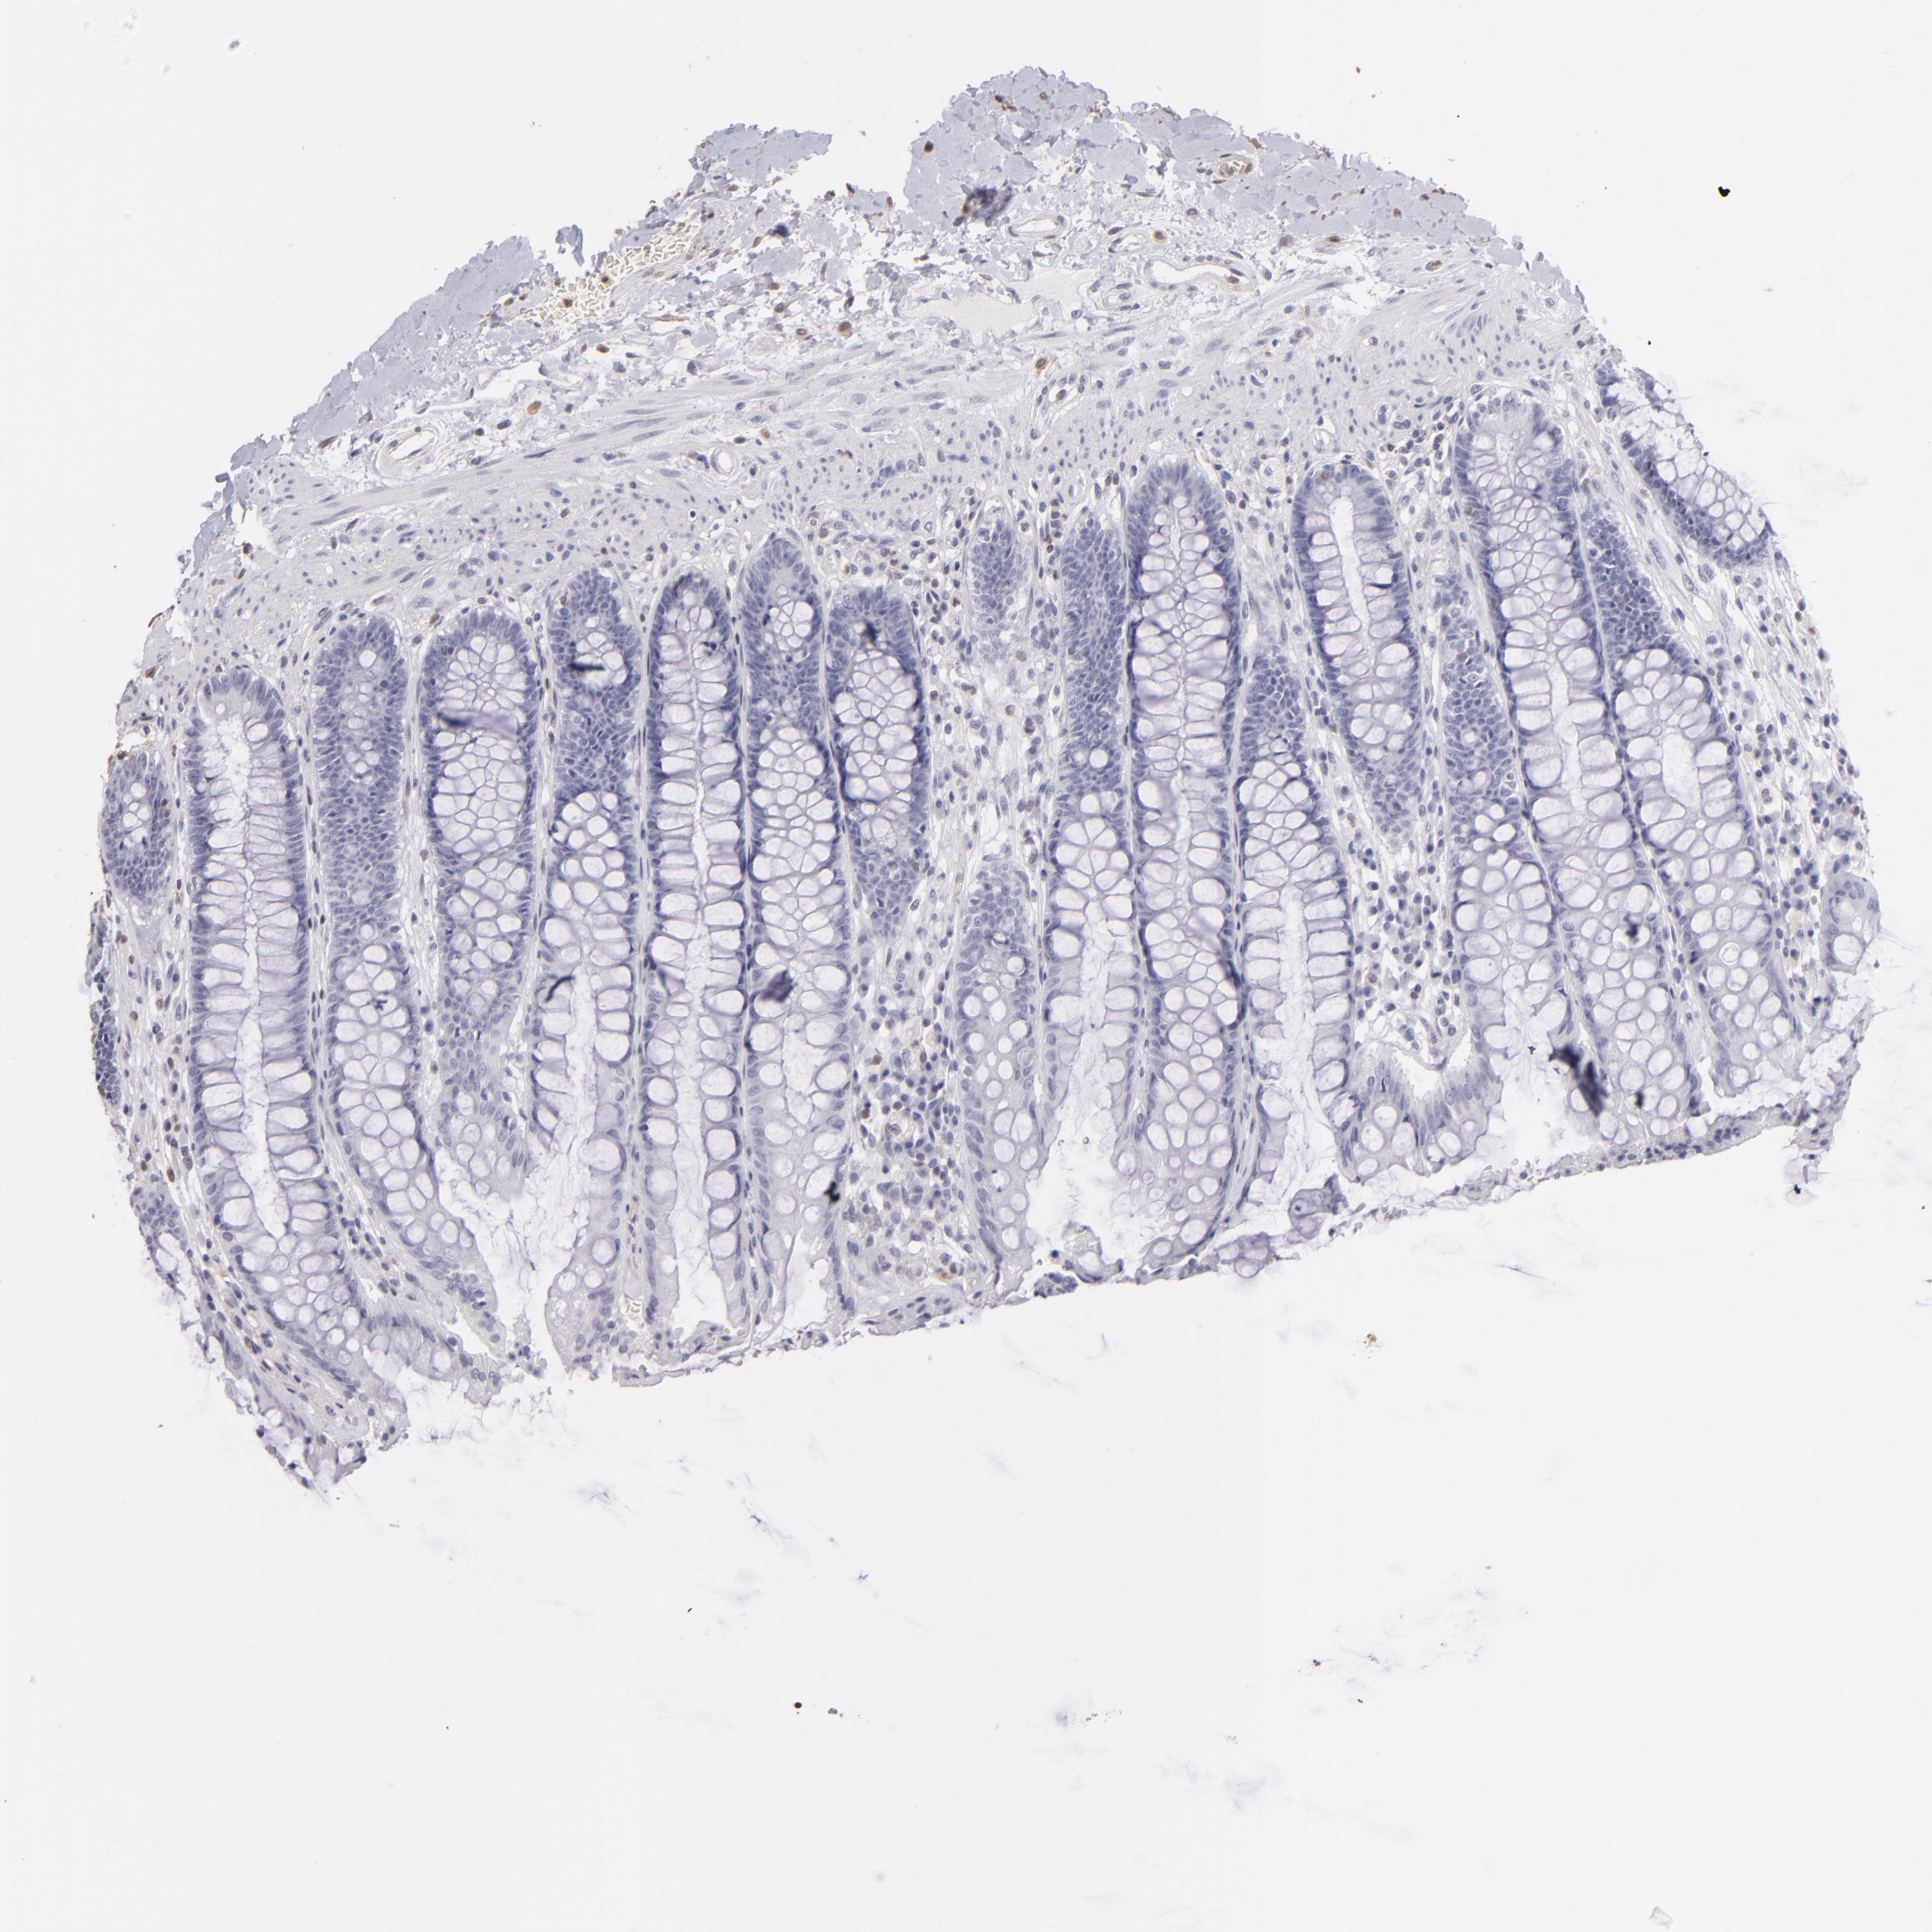

S100A2